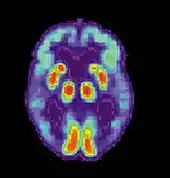

Alzheimer's disease

Alzheimer's disease (AD) is a progressive, degenerative and fatal brain disease, in which cell to cell connections in the brain are lost. Alzheimer's disease is the most common form of dementia.[2] Globally approximately 1–5% of the population is affected by Alzheimer's disease.[3] Women are disproportionately affected by Alzheimer's disease. The evidence suggests that women with AD display more severe cognitive impairment relative to age-matched males with AD, as well as a more rapid rate of cognitive decline.[4]

Aging

Normal aging, although not responsible for causing memory disorders, is associated with a decline in cognitive and neural systems including memory (long-term and working memory). Many factors such as genetics and neural degeneration have a part in causing memory disorders. In order to diagnose Alzheimer's disease and dementia early, researchers are trying to find biological markers that can predict these diseases in younger adults. One such marker is a beta-amyloid deposit which is a protein that deposits on the brain as we age. Although 20-33% of healthy elderly adults have these deposits, they are increased in elderly with diagnosed Alzheimer's disease and dementia.[35]

Amyloid plaques associated with Alzheimer's disease that increase in number with age

As seen in the examples above, although memory does degenerate with age, it is not always classified as a memory disorder. The difference in memory between normal aging and a memory disorder is the amount of beta-amyloid deposits, hippocampal neurofibrillary tangles, or amyloid plaques in the cortex. If there is an increased amount, memory connections become blocked, memory functions decrease much more than what is normal for that age and a memory disorder is diagnosed.[35][37]